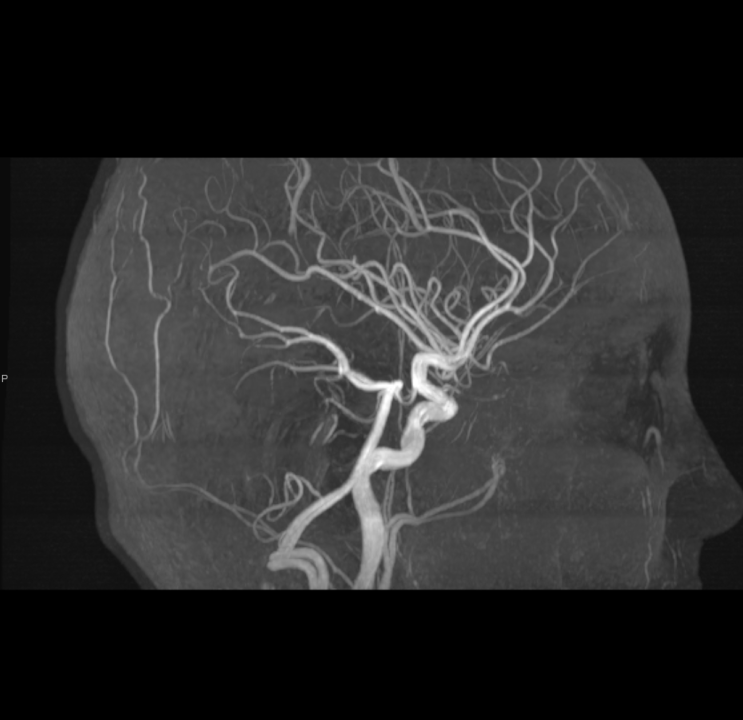

Tijekom Tjedna mozga Poliklinika Affidea Vita daje 20 posto popusta na magnetsku rezonancu!

Povodom obilježavanja Tjedna mozga od 11.

tjedan mozga

MR mozga

MR angiografija